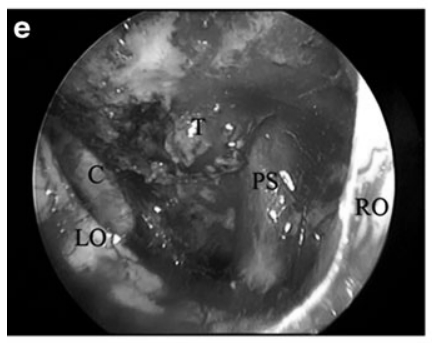

e 30°内镜下探查:可见左侧颈内动脉(c)、左视神经(LO)、右视神经(RO)、垂体柄(PS)及显微镜无法窥及的肿瘤残余(T)。

f 内镜辅助双手操作(bimanual)肿瘤切除。